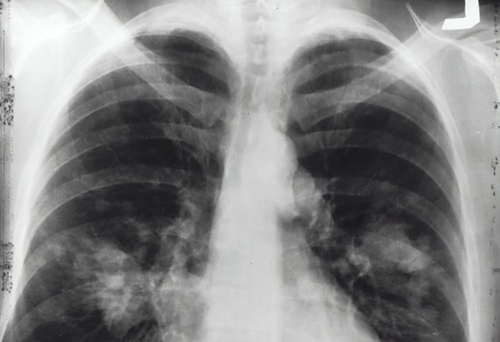

Американские учёные выяснили что случаи рака лёгких у некурящих людей, вызываются опухолями, возникшими в результате генетических мутаций. Ранее выдвигалась точка зрения о том, что эти опухоли - следствие неблагоприятных условий работы.

88% опухолей легких развивается у людей курящих, но это значит, что около 12% приходится на долю пациентов, которые не притрагивались к сигаретам. Конечно, часть из них могут быть жертвами пассивного курения, то есть вдыхания табачного дыма от своих близких. Однако Национальный институт здоровья США раскрыл тайну возникновения опухолей лёгких у людей, которые не сталкивались сами с сигаретами и не становились жертвами пассивного курения. Это открытие может помочь в разработке более точных клинических методов лечения опухолей лёгких.

Геномный анализ рака лёгких у людей, которые никогда не курили, показал, что большинство этих опухолей возникают в результате накопления мутаций, вызванных естественными процессами в организме. Результаты исследования опубликованы в журнале Nature Genetics. Учёные увидели, что у никогда не куривших имеются разные подтипы рака легких с различными молекулярными характеристиками и эволюционными процессами. Рак лёгких является ведущей причиной смерти от опухолей во всём мире - ежегодно заболевание диагностируется более чем у 2 млн человек. К экологическим факторам относят воздействия асбеста и радона, загрязнения воздуха и наличие других заболеваний лёгких.

Однако это объясняет лишь часть опухолей лёгких у некурящих. В ходе нового большого эпидемиологического исследования ученые использовали полногеномное секвенирование, чтобы охарактеризовать геномные изменения опухолевой ткани и сопоставить с нормальной тканью 232 никогда не куривших лиц преимущественно европейского происхождения, которые столкнулись с немелкоклеточным раком легкого. Среди них было 189 аденокарцином - наиболее распространённого тип рака легких, 36 карциноидов и 7 других опухолей различных типов.